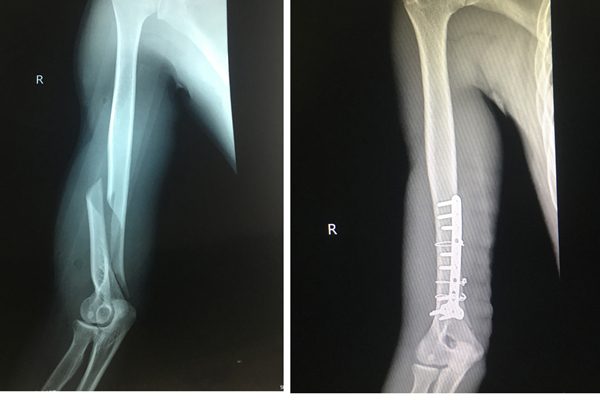

Chơi vật tay, thanh niên 19 tuổi nghe tiếng 'rắc' rồi gãy cánh tay

- Đang chơi vật tay cùng bạn, Cường đột nhiên nghe tiếng “rắc” và cánh tay phải đột nhiên đau nhói, không thể cử động.